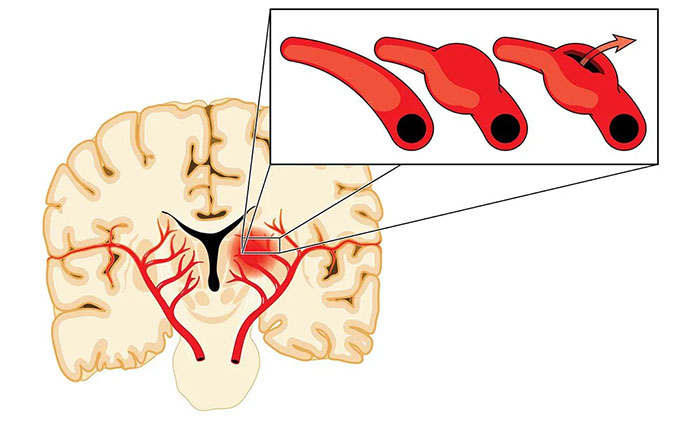

烟雾病的本质是脑血管主干(颈内动脉和大脑中动脉)的狭窄和闭塞,导致灌注异常,引起脑细胞缺血,同时又伴以代偿性颅内异常新生小血管。这些烟雾状血管毕竟不是原始正常的血管,壁很薄,容易破裂出血,这就是烟雾病既容易引起脑梗死,又容易出血的原因。

手术则是目前最主要的烟雾病治疗方式,可分为直接血运重建术、间接血运重建术以及联合(直接+间接)血运重建术。手术治疗的目的,是使用来自颈外动脉系统的血液供应来增加颅内血流,从而改善脑血流量和脑血流储备能力。

“这就好比‘南水北调’,黄河水情不足时,就从长江引流,支援北地,缓解缺水局面。”宫卫东主任形象地打了个比方,通过手术建立由脑外血管向脑内供血的通路,改善脑内血流。脑血供改善以后,对于烟雾状血管的供血需求会逐渐减少,从而降低再次发生脑缺血和脑出血的风险,改善患者的预后。